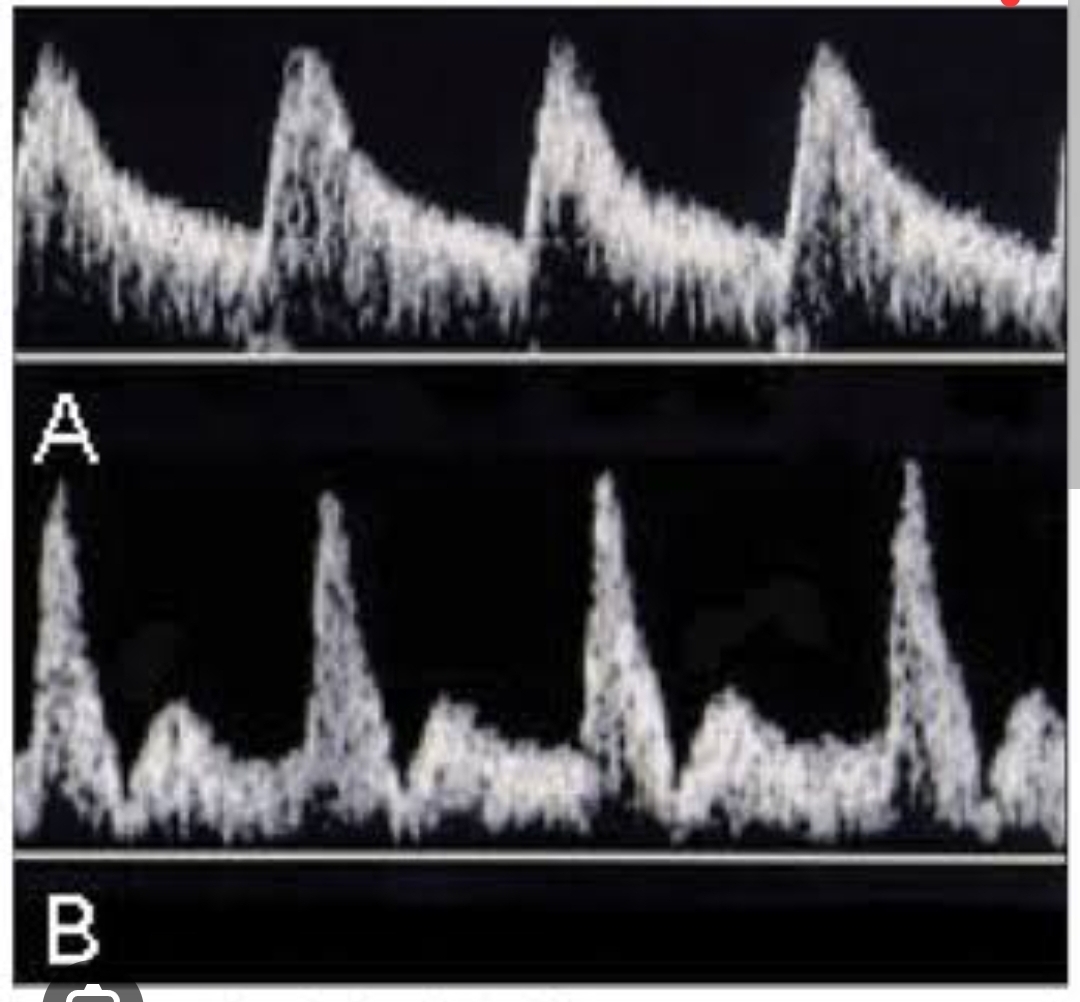

Qual imagem é um doppler normal de arteria uterina e qual é um sinal patológico? Qual é o sinal ? E o que indica?

A

A: normal

B: apresenta incisura ,que se bilateral e presente >26 sem indica aumento de RP e risco de CIUR ou pré eclampsia

Qual doppler de ducto está alterado? Qual alteração? Conduta?

O de baixo apresenta onda A negativa, que indica refluxo venoso, no qual é alto indicatico de IC. Conduta : parto imediato por cesariana